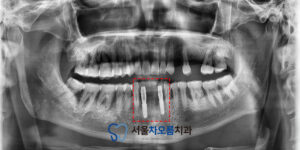

자세한 확인을 위해

파노라마를 촬영해 보니,

예상한 바와 같이 치주질환으로 인해

잇몸뼈가 소실되어 있었습니다.

주변 치아 전부 상황이 안 좋았기 때문에

브릿지를 진행하더라도

예후가 좋지 않을 가능성이 높았습니다.